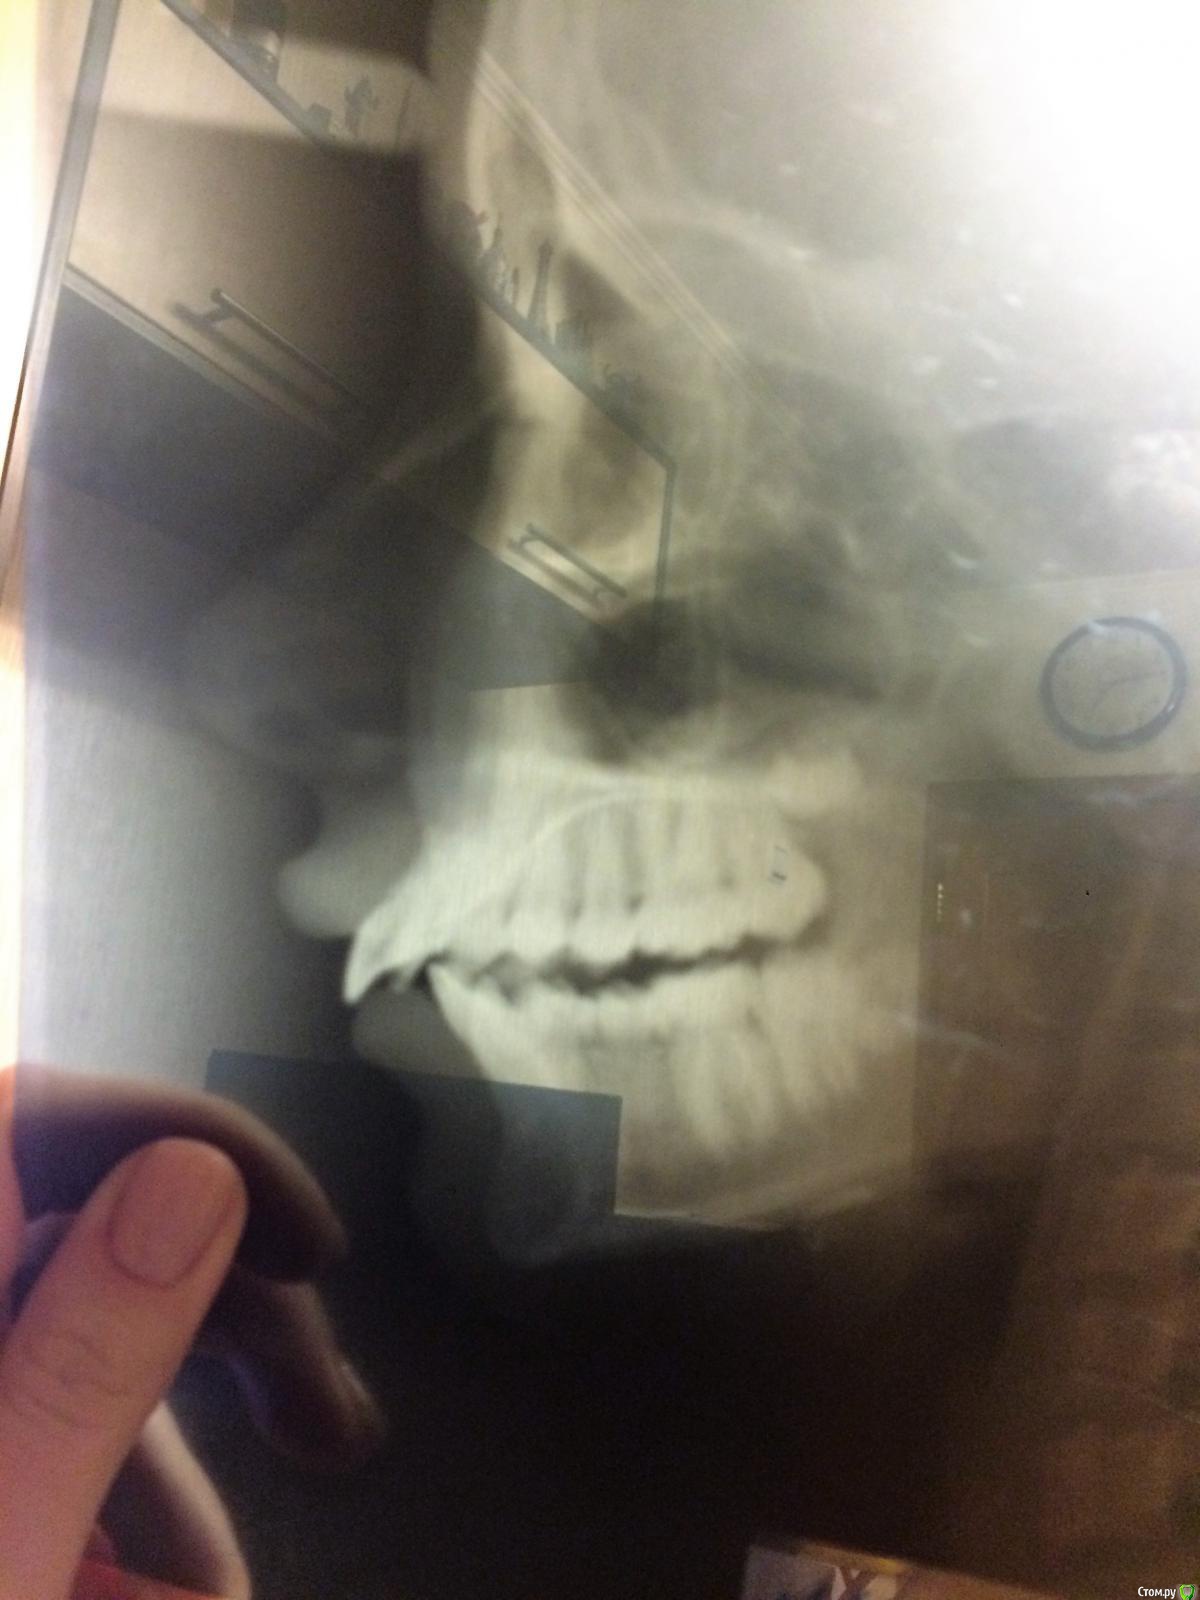

Дарья Меркулова Опубликовано 19 марта, 2017 Поделиться Опубликовано 19 марта, 2017 Дорогие участника форума! У меня вот такая проблема! С 3-х лет наблюдаюсь у стоматолога, носила пластинки. В 12 лет проставили брекеты и вот хочу 9-ый год, зубы то туда, то сюда двигаются, не могут доконца закрыть 1 мм после удаления 4-рок. Кажется, что врач просто обдирает деньги с нас. Уже хочется их просто снять. Потому что постоянно происходит непонятное и ненужное движение зубов. Ортодонт говорит, что так надо!!! 2 года пытались выровнять центральную линию, хотя она была ровная до брекетов. Помогите, может врача сменить? И что? Хотелось, конечно хорошего результата, мне его обещали... А сейчас что? Да уже плюнули на прикус, лишь бы снять сейчас и все доделать. Сейчас: тремы 1 мм слева, справа 5 зуб ушел в десно (его пытаются вытажить) - это уже год делают. Ссылка на комментарий

АнтонТЛТ Опубликовано 19 марта, 2017 Поделиться Опубликовано 19 марта, 2017 Сделайте новые снимки ТРГ и ОПТГ Ссылка на комментарий

Дарья Меркулова Опубликовано 19 марта, 2017 Автор Поделиться Опубликовано 19 марта, 2017 Сделайте новые снимки ТРГ и ОПТГМой стоматолог не планирует этого, говорит, что "всё хорошо" меня больше беспокоит вопрос, как можно уже 2 года закрывать 1 трему в 1 мм, и вытаскивать зуб, который по их же вине ушел в десно. А прикус , пусть уже такой. За 8 лет намучалась Ссылка на комментарий